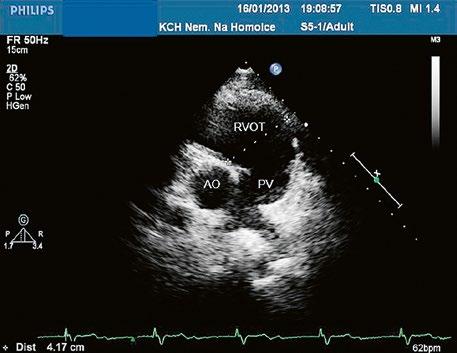

Obr. 45.3 Defekt septa síní typu sinus venosus superior, TEE nad úrovní aortální chlopně, defekt je v horní části septa označen křížky

AO – aorta, LS – levá síň, PS – pravá síň

Obr. 45.4 Defekt typu sinus venosus superior s levopravým zkratem v barevném dopplerovském mapování. TEE v longitudinální projekci, defekt se nachází v horní části septa, je označen žlutou šipkou, na něj nasedá horní dutá žíla (HDŽ)

AP – plicnice, LS – levá síň, PS – pravá síň